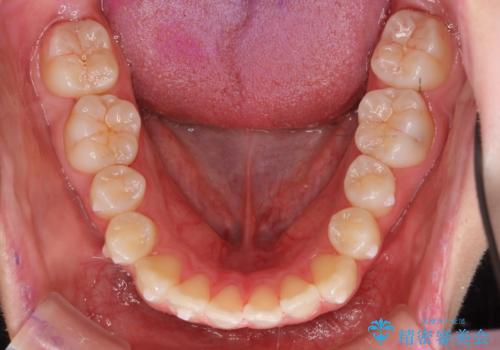

前歯のがたつき 乳歯を抜かずに矯正

- 前歯のがたつきを主訴に来院。

右上に乳歯が残っていましたが、後継永久歯がないため、抜かずに矯正しました。

乳歯の部分が反対咬合でしたが、歯列矯正で被蓋が改善するように移動させました。

右上の乳歯は移動させましたが、幸い矯正後にぐらつくこともなく、そのまま抜けるまで使うことにしました。